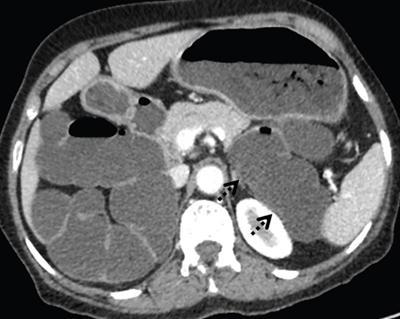

Image

Axial contrast-enhanced computed tomography (CECT) image showing short truncated pancreas with the absence of body and tail of pancreas. Small intestinal loops are seen in the pancreatic bed suggestive of dorsal pancreatic agenesis.